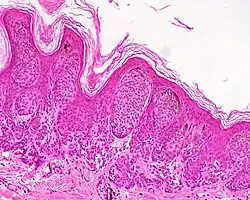

Melanocytic nevi can mainly be classified by depth, being congenital versus acquired, and/or specific dermatoscopic or histopathologic patterns:

- Depth

| Depth class | Location of nevus cells | Other characteristics | Image | ICD code |

|---|---|---|---|---|

| Junctional nevus | Along the junction of the epidermis and the underlying dermis.[15] | May be colored and slightly raised.[16] |

|

ICD10: D22 ICDO: M8740/0 |

| Compound nevus | Both the epidermis and dermis.[17] |

ICD10: D22 (ILDS D22.L14) ICDO: 8760/0 | |

| Intradermal nevus | Within the dermis. | A classic mole or birthmark. It typically appears as an elevated, dome-shaped bump on the surface of the skin.[3][4] |